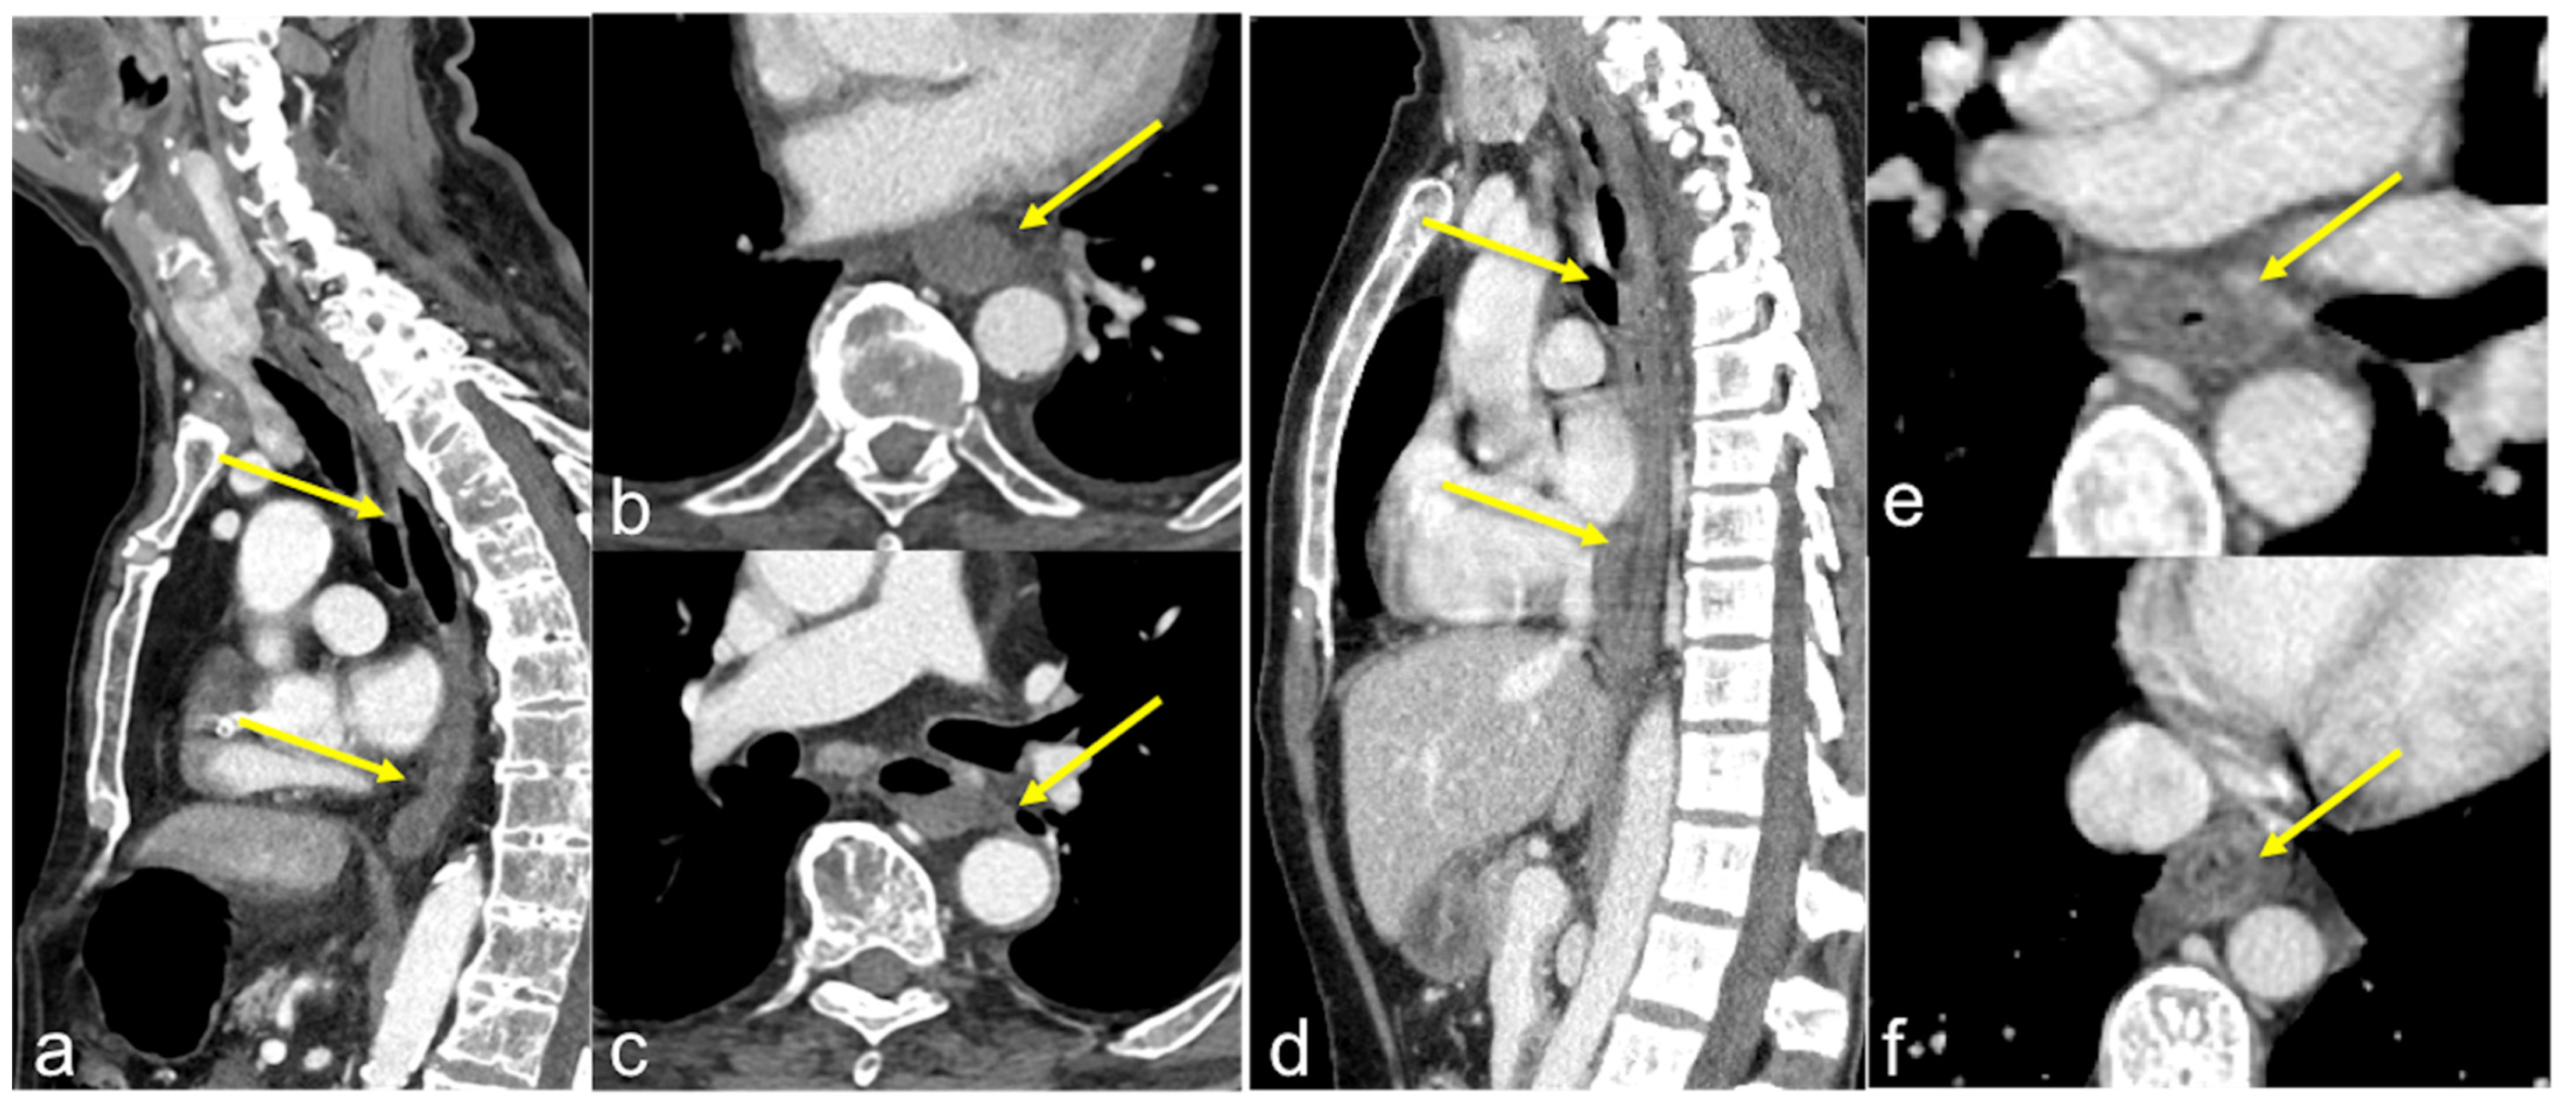

| Oesophageal diverticulum (Figure 24) | Asymptomatic bleeding. | Haemorrhage in a focal herniation of the mucosa through a site of weakness in the muscle layer. |